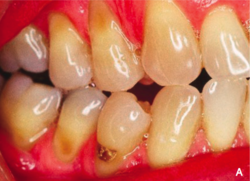

Abrasion occurring on the cervical margins from the effects of friction from toothbrushing and abrasive toothpastes